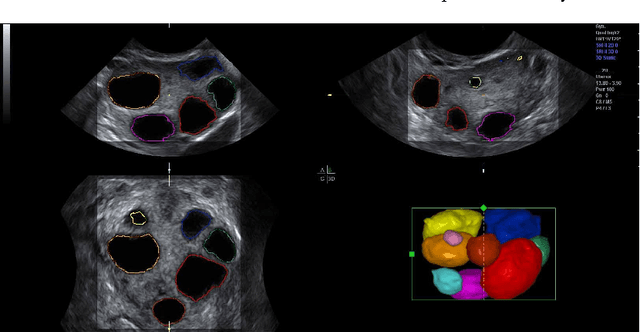

Abstract:Ultrasound is one of the most frequently used imaging modality in medicine. The high spatial resolution, its interactive nature and non-invasiveness makes it the first choice in many examinations. Image interpretation is one of ultrasound's main challenges. Much training is required to obtain a confident skill level in ultrasound-based diagnostics. State-of-the-art graphics techniques is needed to provide meaningful visualizations of ultrasound in real-time. In this paper we present the process-pipeline for ultrasound visualization, including an overview of the tasks performed in the specific steps. To provide an insight into the trends of ultrasound visualization research, we have selected a set of significant publications and divided them into a technique-based taxonomy covering the topics pre-processing, segmentation, registration, rendering and augmented reality. For the different technique types we discuss the difference between ultrasound-based techniques and techniques for other modalities.